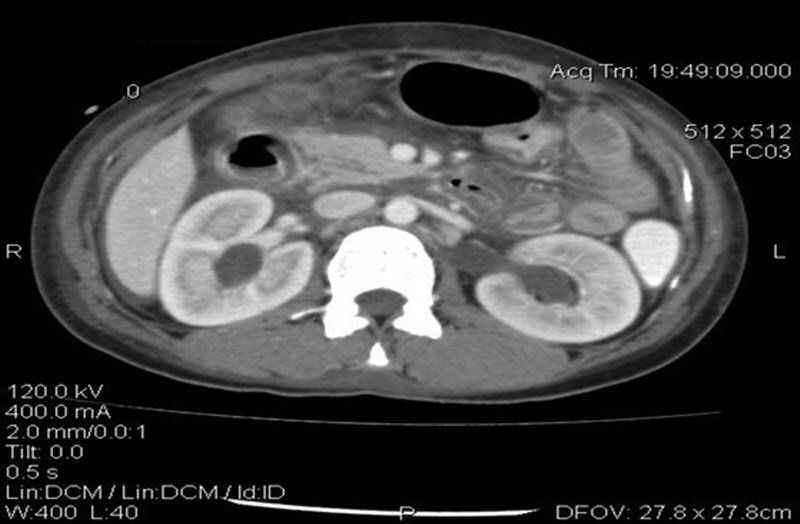

癌胚抗原(CEA)水平正常,但CA-125水平升高为93.5μg/ml(正常范围,0~35μg/ml)。进行腹部和盆腔的CT扫描,证实存在中度腹水和腹膜结节(图2)。膀胱壁和肠壁增厚(图3)。双侧肾积水和多个扩大的主动脉旁淋巴结也可见(图4)。

图4 腹部增强CT显示双侧肾积水